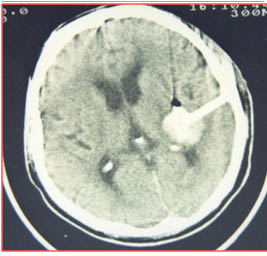

術(shù)后第1天

術(shù)后第10天